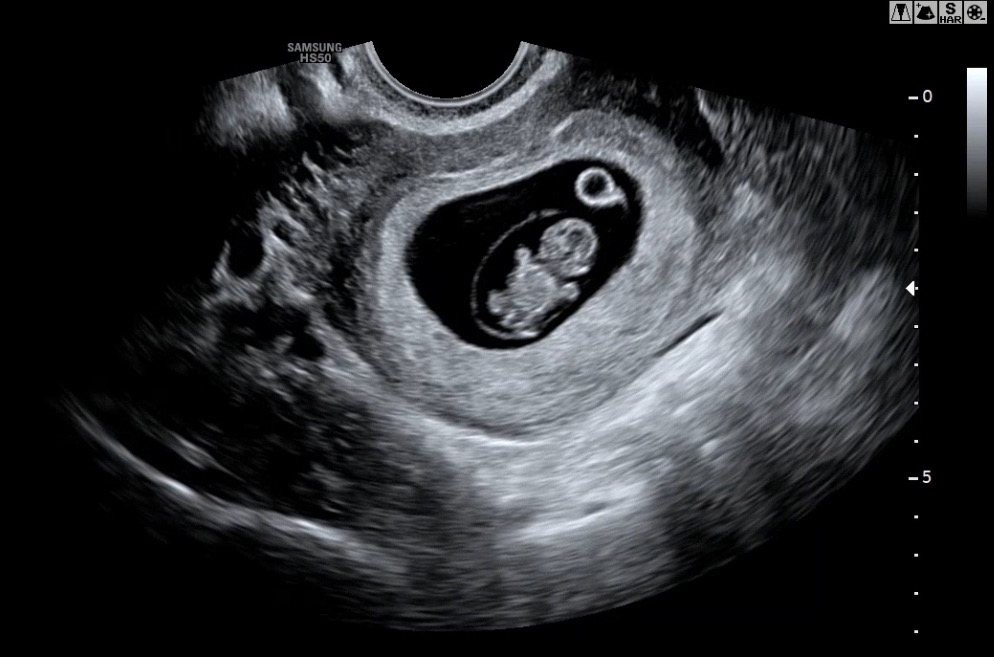

8주차 젤리곰 보고왔어요

팔다리가 뿅뿅 생겼어요! 생각했던 것보다 더 귀엽더라구요ㅎㅎㅎ